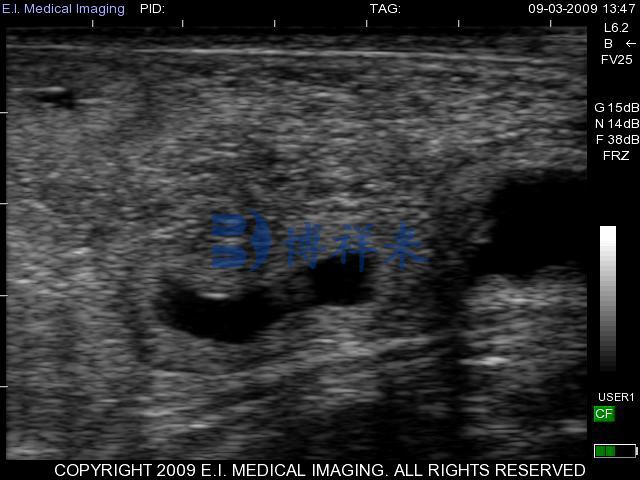

兽用B超机,亦称兽用B型超声仪,是一种专为动物设计的超声波成像设备。通过向动物体内发送高频声波并接收其反射波,兽用B超机能够在显示屏上清晰呈现动物体内的结构图像,从而实现早期妊娠检测、胎儿发育观察、生殖器官检查等多项功能。